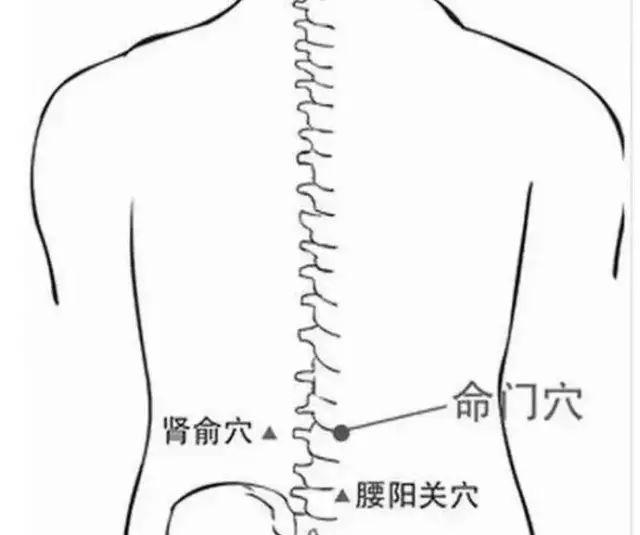

- 腰眼穴为外奇穴,在腰部,第4腰椎棘突下,旁开约3.5寸的凹陷中.

- 肾俞穴在背部腰眼处,即第二腰椎棘突往上两椎体,旁开1.5寸位置.

- 腰眼:第四腰椎棘突下旁开3至4寸